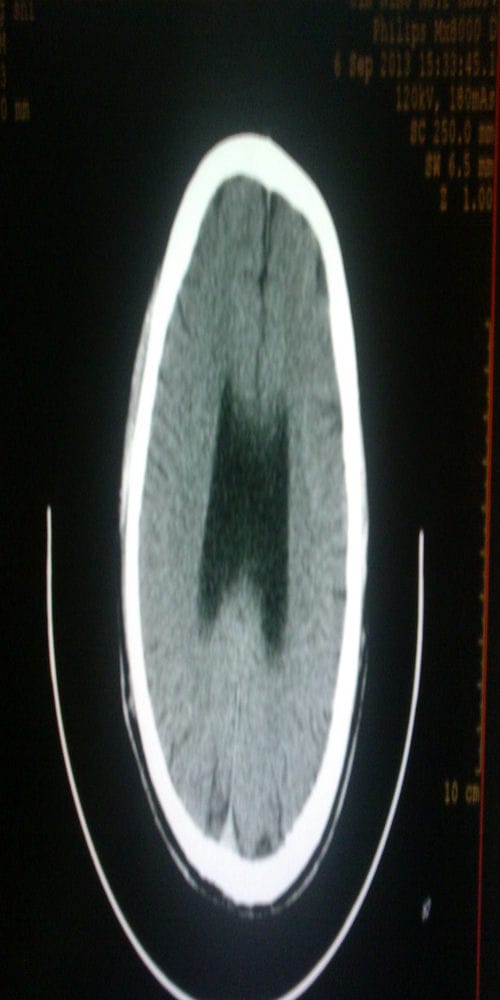

螺旋CT(SCT):螺旋CT扫描是在旋转式扫描基础上,通过滑环技术与扫描床连续平直移动而实现的,管球旋转和连续动床同时进行,使X线扫描的轨迹呈螺旋状,因而称为螺旋扫描。

HRCT:高分辨CT,为薄层(1~2mm)扫描及高分辨力算法重建图像的检查技术。